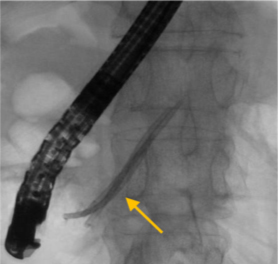

【内視鏡による膵管ステントの留置】

膵管の狭いところ(狭窄)を広げるために、プラスチック製のステント(矢印)を内視鏡を使って留置する。写真は3本のステントが留置されている。